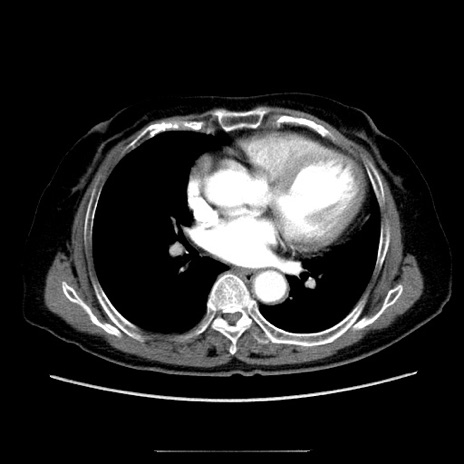

冠状断像

【症例】70歳代女性

【主訴】お腹が張る

【現病歴】1週間くらい前から腹部膨満の自覚あり。昨日夜から増悪したため、本日救急外来受診。

【身体所見】意識清明、BT 36.5℃、BP 165/106mmHg、HR 80bpm、SpO2 98%、腹部:膨満、軟、自発痛・圧痛なし、触診にて不快感あり、腸蠕動音:減弱

【データ】WBC 12600、CRP 1.04